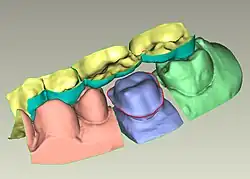

La conception assistée par ordinateur trouve une application en odontologie. La CAO fait suite à l'étape d'acquisition numérique, réalisée grâce à un dispositif de numérisation associé à des programmes de traitement des données. Plusieurs solutions de numérisation existent, comme une caméra intra-orale (empreinte numérique des arcades dentaires du patient) ou un scanner de modèle en plâtre.

L'étape de CAO se compose de programmes informatiques qui permettent la conception de la restauration prothétique virtuelle (couronne, bridge, onlay, prothèse amovible) sur le modèle virtuel correspondant aux arcades du patients. La conception est réalisée via l'utilisation de dents et de restaurations types provenant d'une base de données. La restauration est adaptée au modèle via des modules d’aide à la conception permettant la création des contacts avec les dents adjacentes et antagonistes (simulation de l’occlusion), la définition de l'espacement entre la restauration et le modèle, le tracé de la zone d'arrêt de la prothèse (limite cervicale) etc[5].